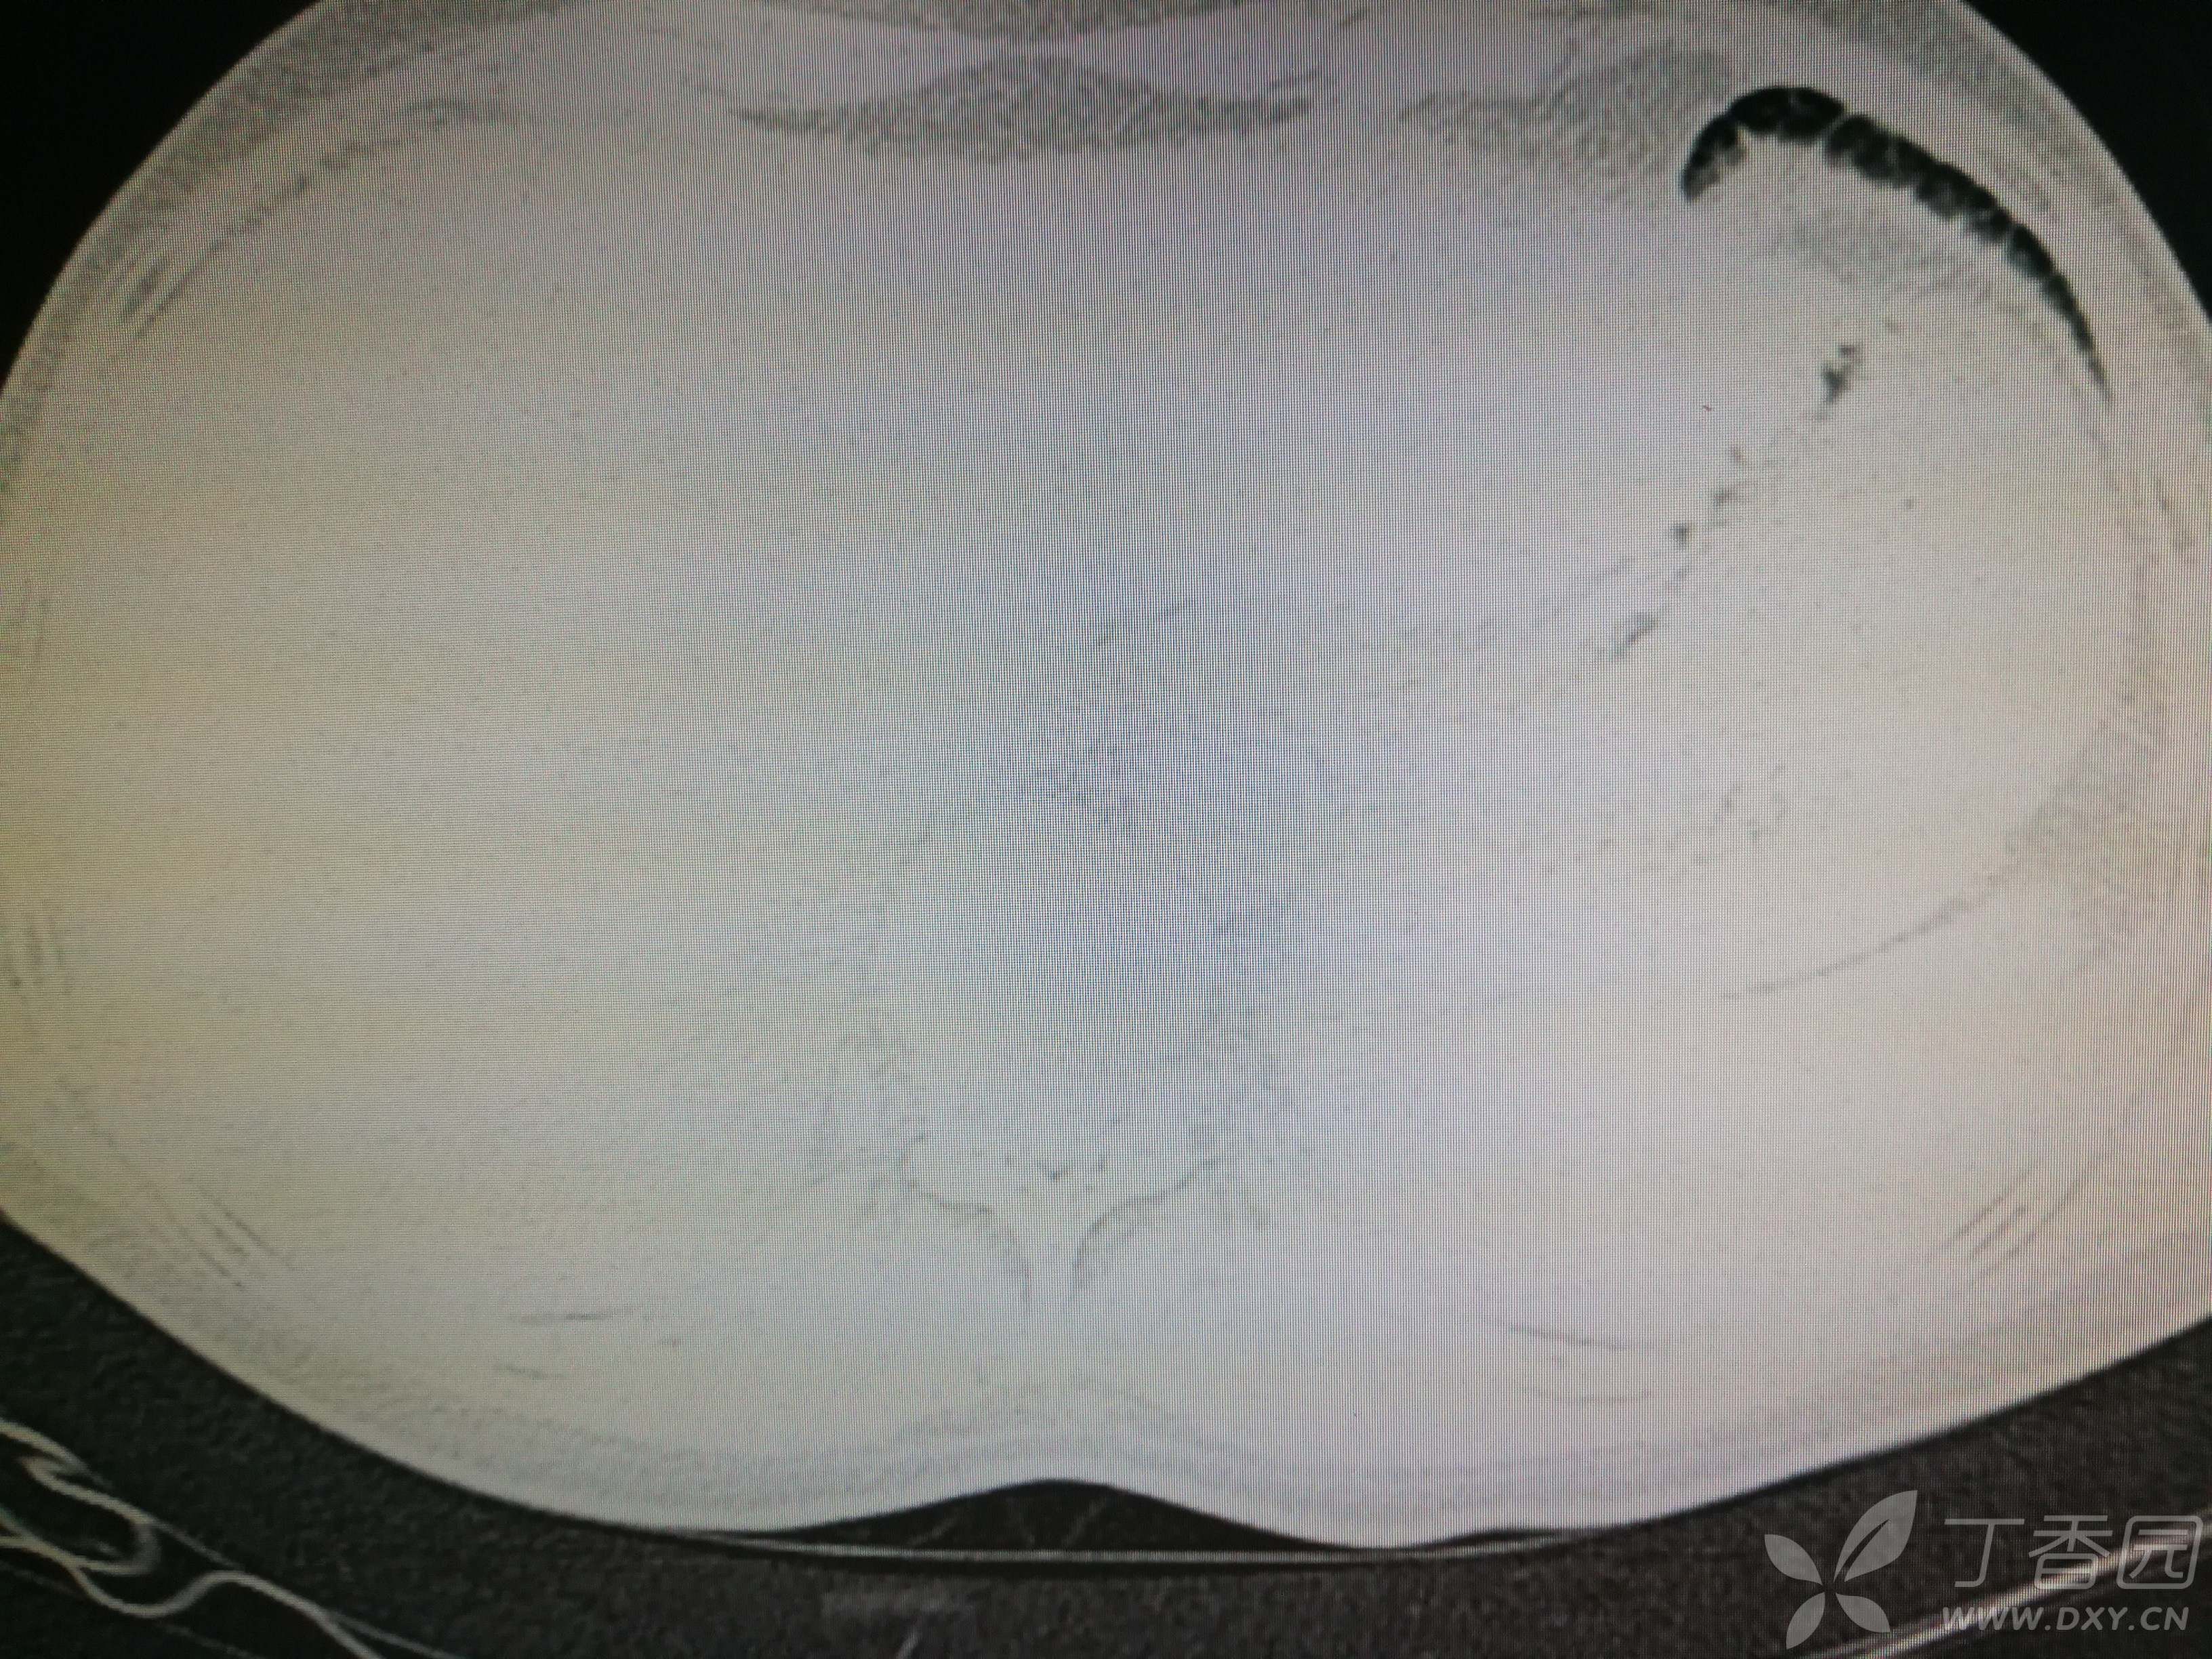

给予低分子肝素钙针抗凝、七叶皂苷钠针消肿及骨牵引固定等等治疗。入院后第四天行“左侧股骨下段骨折切开复位内固定术”(术前查双下肢彩超:双下肢深静脉血流通畅),手术顺利,术后予预防感染、预防血栓形成等治疗。术后患者无明显发热,生命体征平稳。术后第四天复查血常规:白细胞13.4×109/L,血红蛋白84g/L,血小板在正常范围。生化:白蛋白35.7g/L,余无明显异常。当天,患者开始出现轻度胸闷气急,可耐受。术后第五天患者胸闷气急加重,无胸痛,无背痛,无咯血,无意识障碍,无头晕头痛,无恶心呕吐等,急查凝血功能:纤维蛋白原降解产物12mg/L,D二聚体4000ug/L,余无明显异常。查动脉血气分析:pH7.52,氧分压62mmHg,二氧化碳分压30mmHg,碱剩余1.8mmol/L,乳酸1.0mm/L,血红蛋白86g/L。查胸部CT见下(先视频后图片):